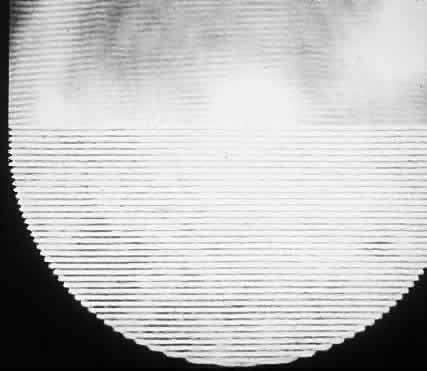

Figure 12 contrasts the patterns seen by patients with normal vision and patients with cataracts.

Fig. 12. Interference fringes as they appear normally (top) and with double images focused on tissue paper placed over camera lens (bottom). Cataract patients may see continuously changing fringe patterns similar to those patterns on the bottom. (Green DG: Testing the vision of cataract patients by means of laser generated interference fringes. Science 16(June):5, 1970 [cover photo]. Copyright © 1970, American Association for the Advancement of Science)